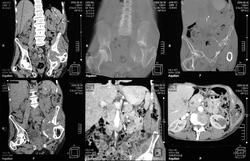

Здесь представлены КТ срезы брюшной полости и таза с контрастированием, выполненные через 2 года после травмы.

Реконструкции

на серии кт определяются в средней трети левой почки ,латерально от ее ворот определяется гиповаскулярный участок с четкими ровными контурами .с поддавливанием чашечно-лоханочной системы,ограниченый капсулой почки ,неправильной вытянутой формы ,который в поздней венозной фазе не изменяет своей визуализации (д.д между кистой и кистозной формой почечно-клеточного рака).латерально от левой почки в мягких тканях определяется большой участок со сниженной денситометрической плотностью,размерами - 53х117мм ,с включениями газа и кольцом периферического усиления,с дренажом(вероятнее всего крупный абсцесс).печень увеличена в размере,селезенка с включениями кальция .размеры поджелудочной железы в пределах нормы,холедох и вирсунгов проток без патологии.надпочечники нормальных размеров,без изменений.в области левого тазобедреного сустава определяется участок деструкции с разрушением вертлужной впадины ,головки и шейки бедренной кости ,смещением повздошной кости вверх и латерально на 111.1мм,с фрагментом головки левой бедренной кости .в левой повздошной кости определяются гиперостоз с обширным участком остеосклероза и мелкими участками остеолитической деструкции (смешанный тип).аналогичные остеолитические изменения в крыле правой повздошной кости и в головке правой бедренной кости (сужу по 3d).по медиальному контуру средней трети тела поздошной кости определяется разрушение замыкательной пластинки с вовлечением губчатого вещества на большом протяжении,в крыше и самой вертлужной впадине с мягкотканным компонентом ,с участками пониженной денситометричской плотности (вероятнее всего участки некроза),с мелкими костными фрагментами (что косвенно может подтверждать рост изнутри снаружу),с поддавливанием на большом протяжении органов малого таза,латерально -левая стенка мочевого пузыря утолщена.вывод :такие изменения могут быть как первичного так и метастатического характера .первопричина протрузии возможно врожденного характера(дисплазия) ,затем перелом усугубил процесс(посттравматическая протрузия).меня настораживает тот момент,что изменения в повздошной кости напоминают хронический остемиелит изначально .а затем появились изменения ,сильно напоминающие озлакочествление+изолированно крупный абсцесс